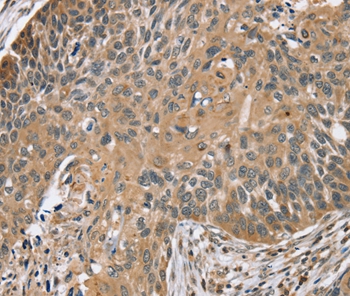

Immunohistochemical analysis of paraffin-embedded Human thyroid cancer tissue using #37876 at dilution 1/45.

Immunohistochemical analysis of paraffin-embedded Human esophagus cancer tissue using #37876 at dilution 1/45.